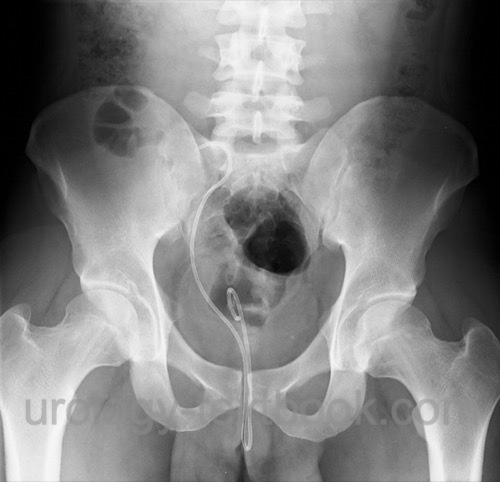

Dislocation:

Cranial migration (distal end slips into the ureter) causes obstruction. Kaudal migration leads to incontinence if the distal end passes the external urinary sphincters [fig. dislocated stent].

![]() |